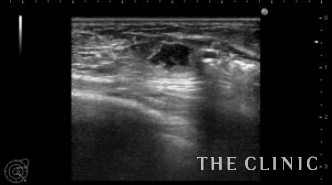

他院でヒアルロン酸豊胸を行った方ですが、炎症のためヒアルロン酸の周囲に非常に厚い被膜が形成され、瘢痕化していました。

しこりは両側の乳房全体にあり、一部は以前ヒアルロニダーゼで吸引しました。

被膜は肥厚して中心にわずかにヒアルロン酸があります。

ヒアルロニダーゼで溶解して吸引しましたが、被膜は残存しています。

エコーとの比較です。

このしこりは内腔がありヒアルロン酸がありました。

ヒアルロン酸注入によるしこりのエコー診断カルテ